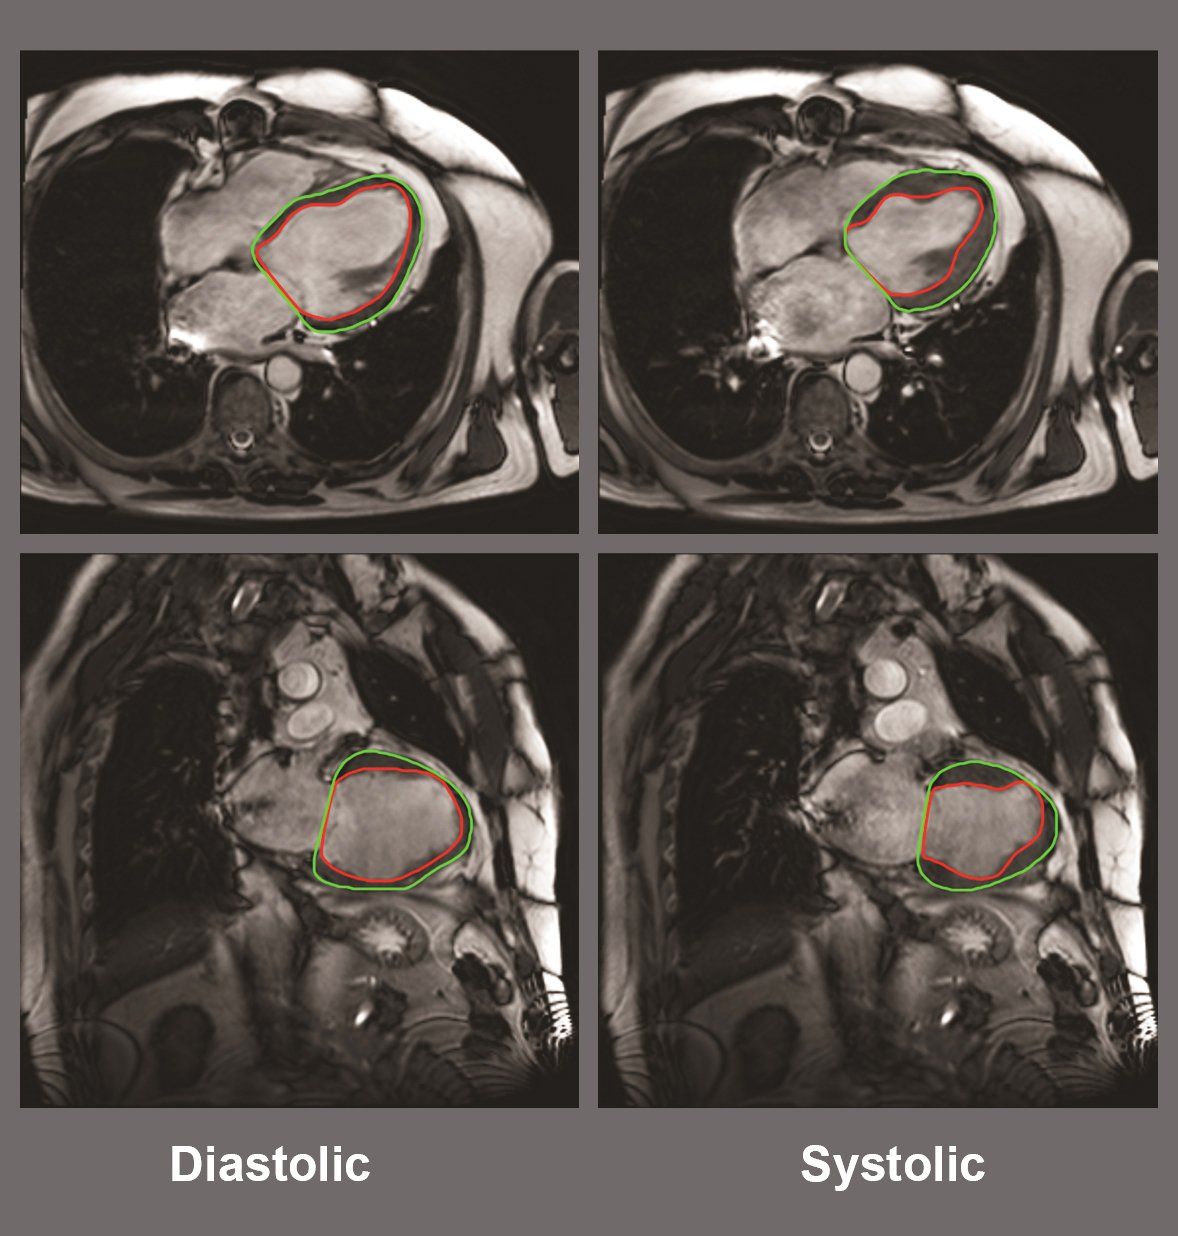

centrale aanpak voor het

invoeren, opslaan en analyseren van de data. Inclusief een geautomatiseerde analyse van MRI-beelden van hart, bloedvaten en hersenen. Delen van deze aanpak, worden inmiddels ook toegepast in andere (CVON) studies.